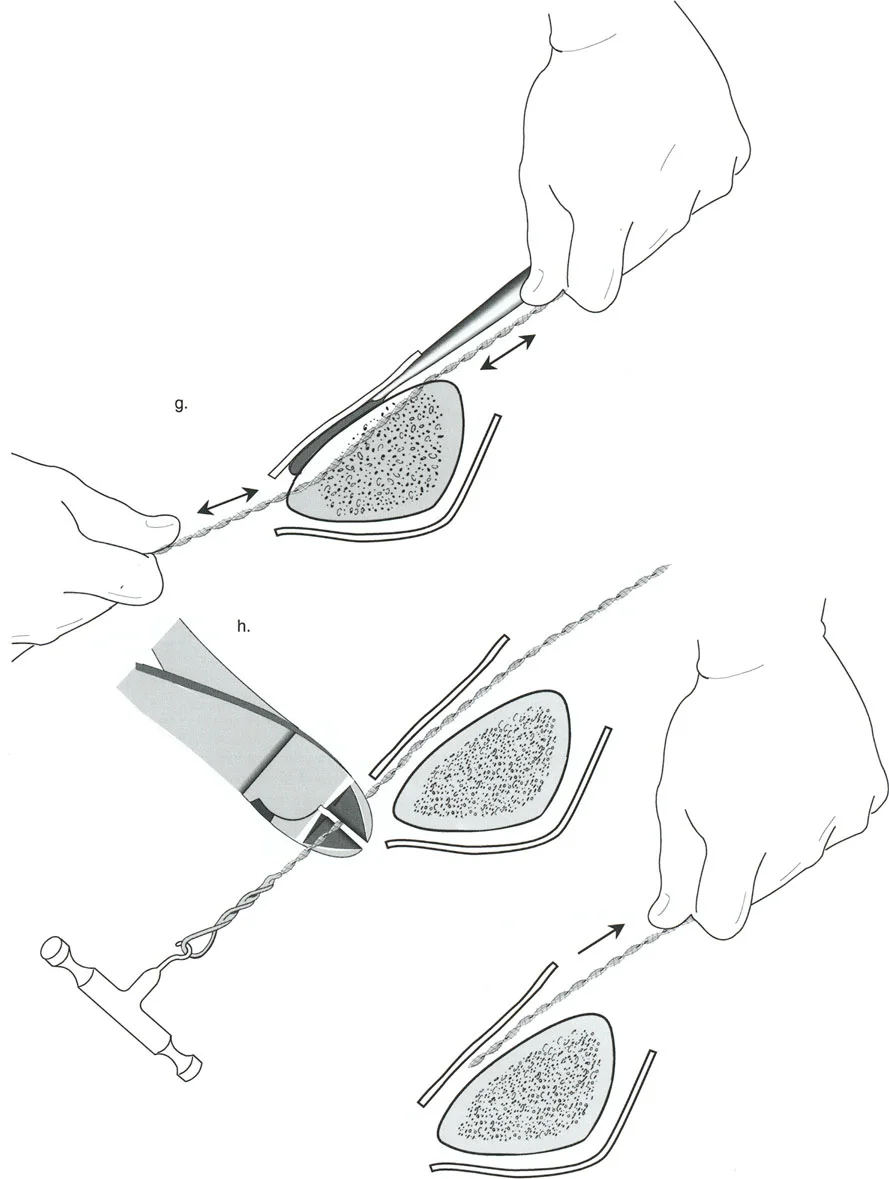

قيود الأسلاك والدبابيس في القاعدة 2

لتحقيق هذه الترجمة الضرورية والمقصودة بسلاسة باستخدام إطار دائري كامل الأسلاك، يلزم استخدام أسلاك الزيتون المعاكسة (counter-opposed olive wires). تعمل أسلاك الزيتون كقوى سحب ديناميكية، تسحب قطعة العظم على طول الحلقة أثناء فتح المفصلات. بدون أسلاك الزيتون، سيبقى العظم ثابتًا بينما تتحرك الحلقة عبر الأنسجة الرخوة، مما يسبب نخرًا شديدًا في الجلد.

على العكس من ذلك، إذا تم استخدام دبابيس نصفية (مسامير شانز)، فإنها تقيد العظم بطبيعتها بالحلقة. نظرًا لأن الدبابيس النصفية هي أذرع صلبة (مثبتة من طرف واحد بالحلقة ومغروسة في العظم من الطرف الآخر)، فإنها لا تسمح للعظم بالانزلاق على طول محور السلك. هذا يجعل أسلاك الزيتون غير ضرورية للترجمة في منشآت الدبابيس النصفية، ولكنه يتطلب من الجراح التأكد من أن الدبابيس النصفية قوية بما يكفي (عادةً دبابيس بقطر 5 مم أو 6 مم مطلية بهيدروكسي أباتيت) لتحمل لحظات الانحناء الناتجة عن الترجمة.

نصائح جراحية للمنشآت القريبة من المفصل

| تقابل الأسلاك | استخدم ما لا يقل عن سلكين زيتون متقابلين لكل قطعة إذا كنت تتجنب الدبابيس النصفية. | الأسلاك الزيتون الفردية ستسبب قصًا ودورانًا غير مرغوب فيه حول محور السلك. |